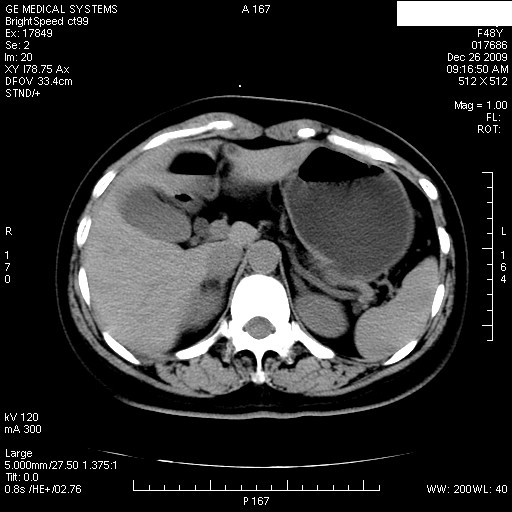

患者女性 48岁 突发上腹部疼痛,无其他不适,查体莫菲氏征阴性,ct示:胆囊炎,胆总管上端轻度扩张

图像是否为同一人?还是同一人不同时段的图像?胆结石。

胆囊结石,十二指肠占位?

1)肝内外胆管扩张,原因待查。2)胆囊内药物沉积?